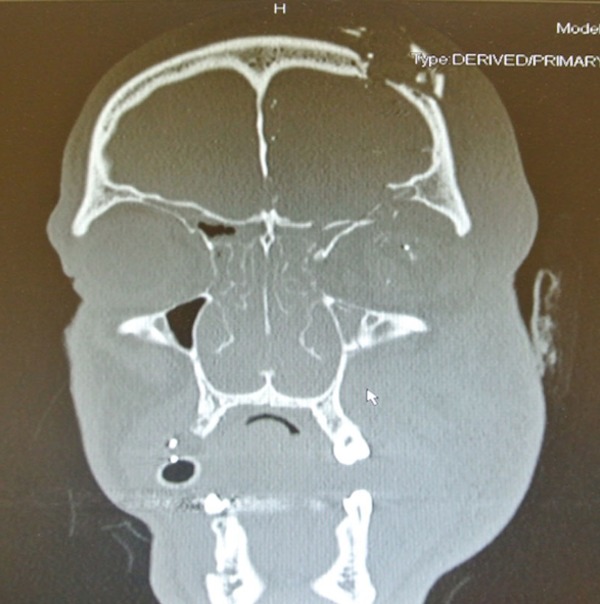

gif_animation 実弾が入った銃でロシアンルーレットをし、自分の頭を撃ち抜いたアルバニア人の20歳の男性。数多くの手術を受けながら30日間入院、一命を取り留めた。[3]img